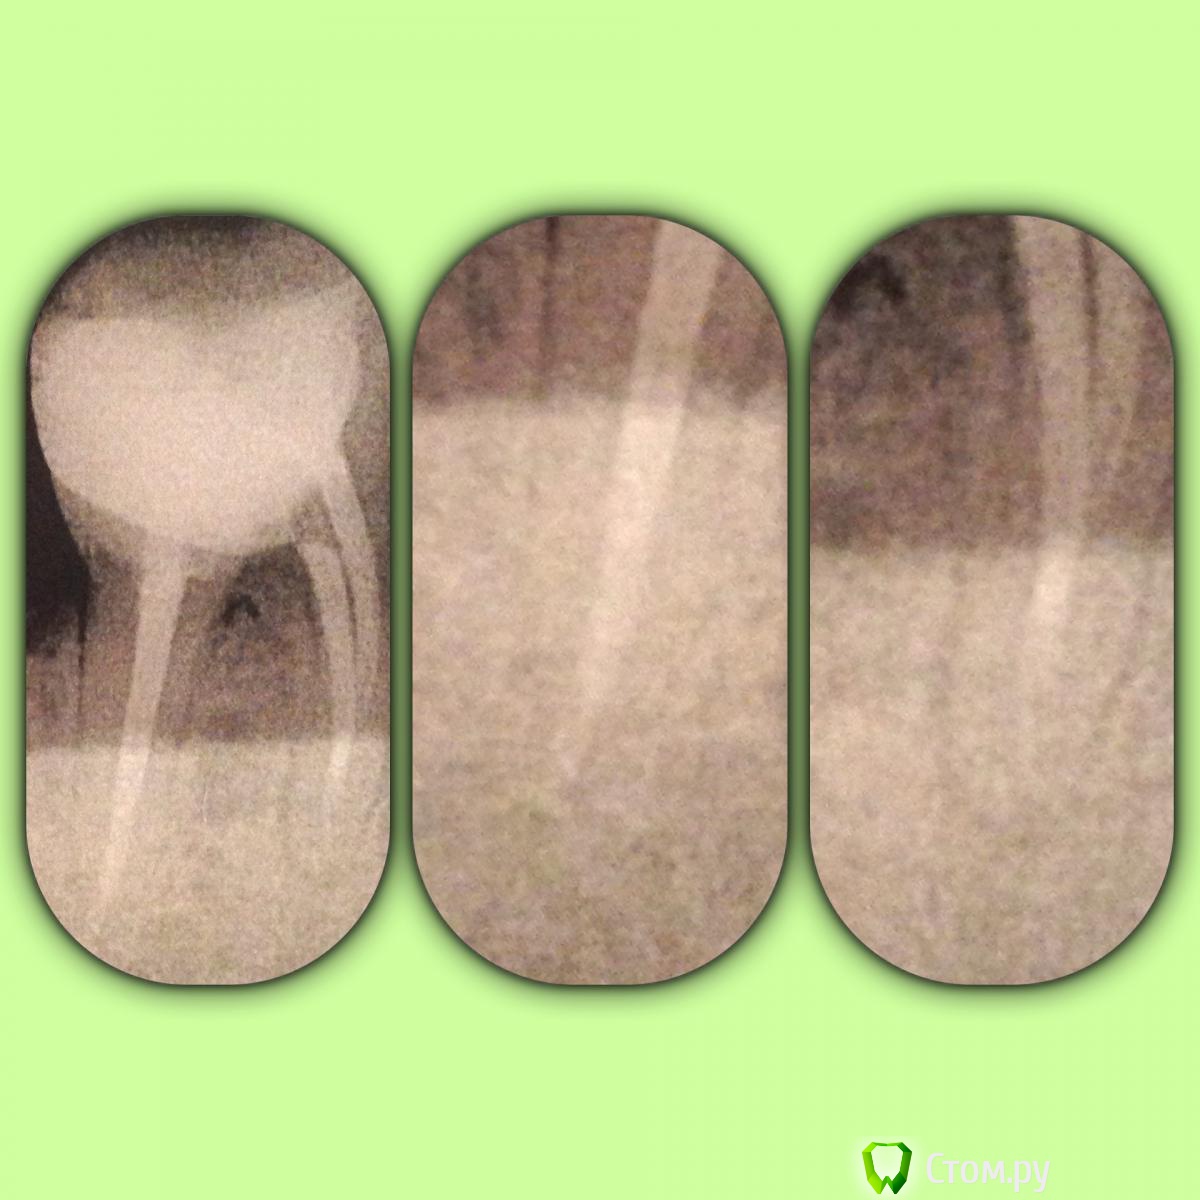

SSTi Опубликовано 23 июня, 2014 Автор Поделиться Опубликовано 23 июня, 2014 Зуб мамы. Июнь 2013. 46. Снимка до нет. Потерял где-то. Пломба дистально была разрушена. Глубокий кариес, леченый много лет назад, стал периодонтитом. Нашел 4 канала. 2 дистальных сходятся. По дурости и молодости в дистальном штифт(мой косяк). Сегодня сделал снимок. Вроде динамика на медиальном лучше, чем на дистальном... Планируем достать штифт, сделать вкв и коронку. Но. Зуб немного реагирует (очень редко) на горячее. Лечил как положено(коффер, хлорка и т.д.). В общем вопрос вот в чем. Лезть в каналы перед вкв или нет? Ссылка на комментарий

faity Опубликовано 23 июня, 2014 Поделиться Опубликовано 23 июня, 2014 межкорневое смотрел, на болезненность? на старом снимке есть затемнение, на новых тоже. Ссылка на комментарий

faity Опубликовано 23 июня, 2014 Поделиться Опубликовано 23 июня, 2014 Перфо не было никаких точно.не, дружище, я не про перфо, я про кость в межкорневой перегородке, затемнение небольшое есть, а раз нерва нет, а чувствительность есть- ищи проблему в пародонте Ссылка на комментарий

SSTi Опубликовано 23 июня, 2014 Автор Поделиться Опубликовано 23 июня, 2014 Чувствительность есть и на холодное. Я думаю путает с верхним просто. Faity, спасибо. Будем искать. Ну вот почему у своих все всегда не так??))))) Ссылка на комментарий